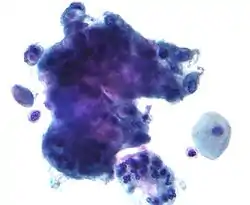

![]() High-grade squamous intraepithelial lesion | |

- High-grade squamous intraepithelial lesion (HGSIL or HSIL)

In a typical scenario, about 0.5% of Pap results are high-grade SIL (HSIL), and less than 0.5% of results indicate cancer; 0.2 to 0.8% of results indicate Atypical Glandular Cells of Undetermined Significance (AGC-NOS).